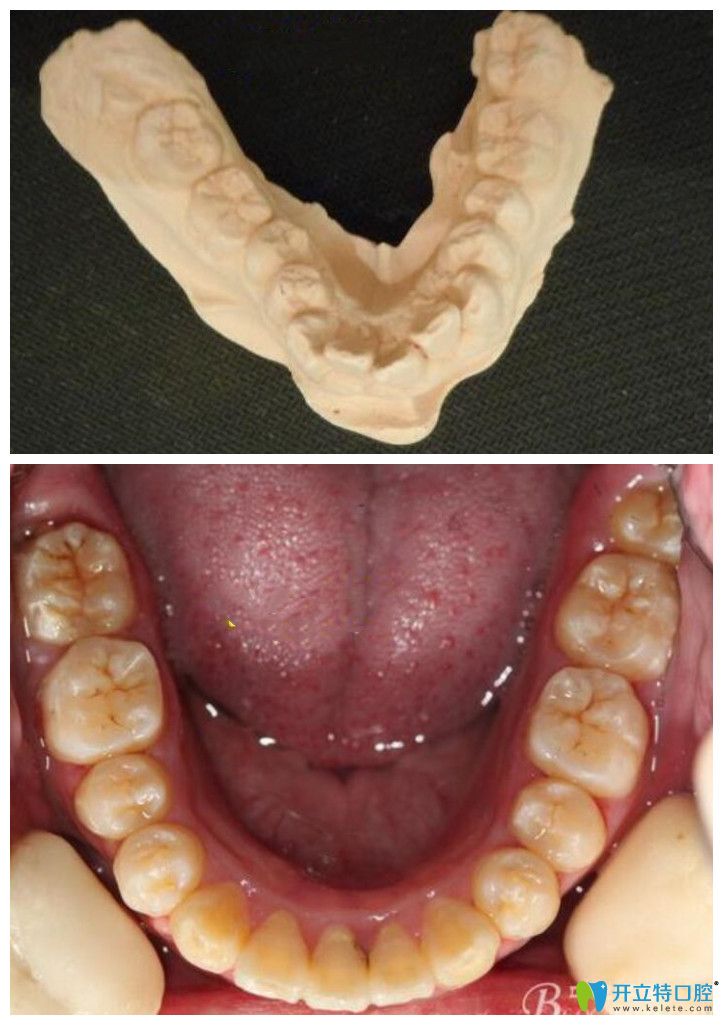

▲牙弓狹窄采用擴(kuò)弓+金屬鋼絲矯正案例